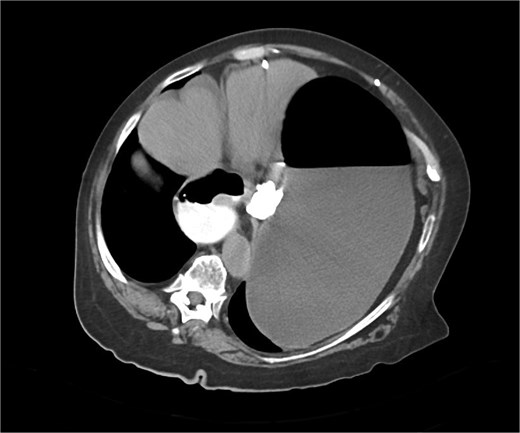

The CT also showed a large ventral hernia in the anterior abdominal wall on the left side, with several entrances and exits for intestinal loops within the hernia. The proximal loops appeared dilated up to 5 cm, with fat stranding and slight fluid between the loops, as well as mild prominence of the mesenteric blood vessels. Distal loops were collapsed, raising suspicion of high-grade obstruction with ischemic bowel involvement (Fig. 5).

CT axial view—obstructed ventral hernia with proximal small bowel loop dilatation.